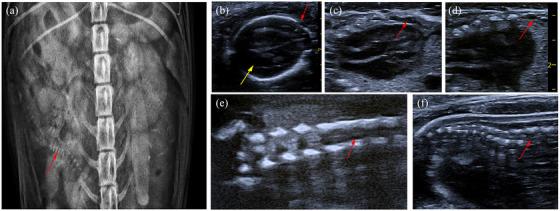

Open spina bifida characterisation in a dog foetus.

Imaging diagnosis--cerebellar displacement and spina bifida in a calf.

Crash sign: new first-trimester sonographic marker of spina bifida.